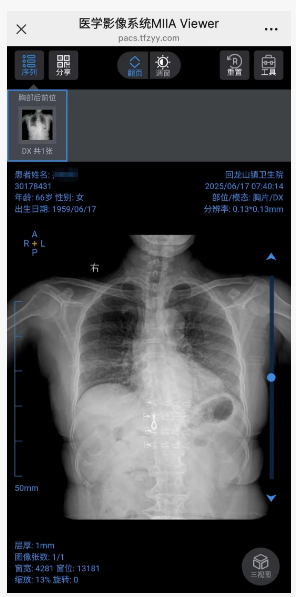

即日起,团风县人民医院“云影像”服务覆盖全县各级医疗机构。患者完成X光、CT、磁共振等检查后,无需排队领取实体胶片,通过手机登录“健康团风”公众号即可随时调阅原始高清影像,彻底解决传统胶片“携带难、易损坏、保存短”的痛点。

医学影像患者服务系统是赋能患者的综合服务平台,提供检前影像检查预约、科普宣教,检后数字影像服务(云胶片)、基于DeepSeek的智能影像报告解读、影像健康档案等多项功能。同时,医生可通过患者分享的二维码快速查看影像并进行后处理操作。该系统大幅提升患者就医体验,避免患者因取胶片、不懂报告术语来回奔波医院的问题。

如何使用“云影像”

- 关注“健康团风”公众号,绑定个人信息

- 点击“云影像查询”

- 输入就诊人个人信息

- 进入报告界面,可以查看检查项目的报告结果